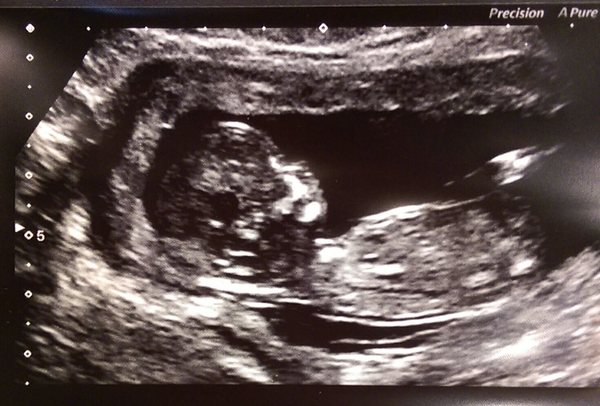

I had a lovely scan yesterday, all looking good althought the baby was not cooperating when it came to measuring the nuchal fold. My dates have been moved forward by a whopping six days so my new official EDD is 5th of Dec.